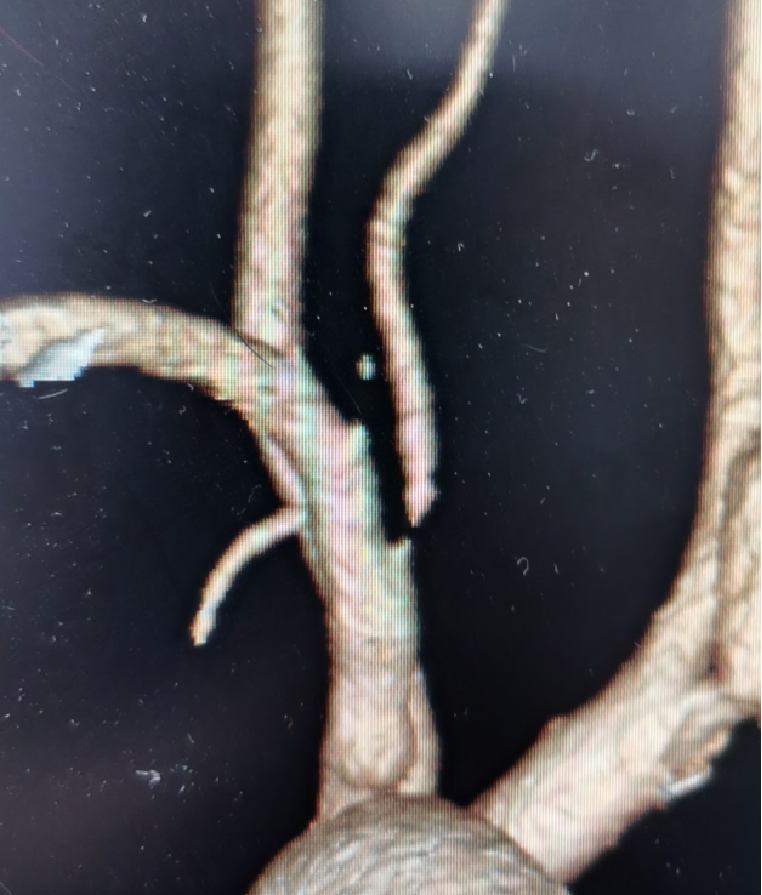

患者王某某,因头晕、左侧肢体无力20余天入院,完善CTA后示右侧椎动脉狭窄,给予椎动脉支架植入血管成形术后,上述症状消失。

右侧椎动脉狭窄